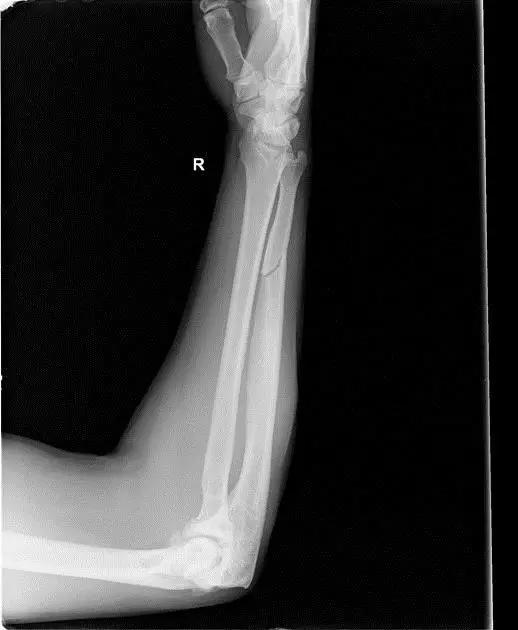

10. Galeazzi 骨折(盖氏骨折)

桡骨干下 1/3 骨折合并尺骨小头脱位。

盖氏骨折正侧位(来源:Orthobullets)

9. Essex-Lopresti 骨折

是桡骨头骨折伴有下尺桡关节脱位,导致骨间膜损伤,桡骨短缩。此种损伤,桡骨头骨折的诊断往往是明确的,容易忽视的是下尺桡关节脱位,特别是早期,下尺桡关节的症状不明显,X 线表示也不明显。

Essex-Lopresti 损伤。前后位(A)和侧位(B)示桡骨头关节内骨折(白色实线箭头);(C~E)伤后 1 个月复诊,患者诉腕关节疼痛,X 线(C,D)发现下尺桡关节脱位,(E)CT 进一步证实损伤的存在 (来源:Radiol Clin North Am. 2015 Jul;53(4):717-36)